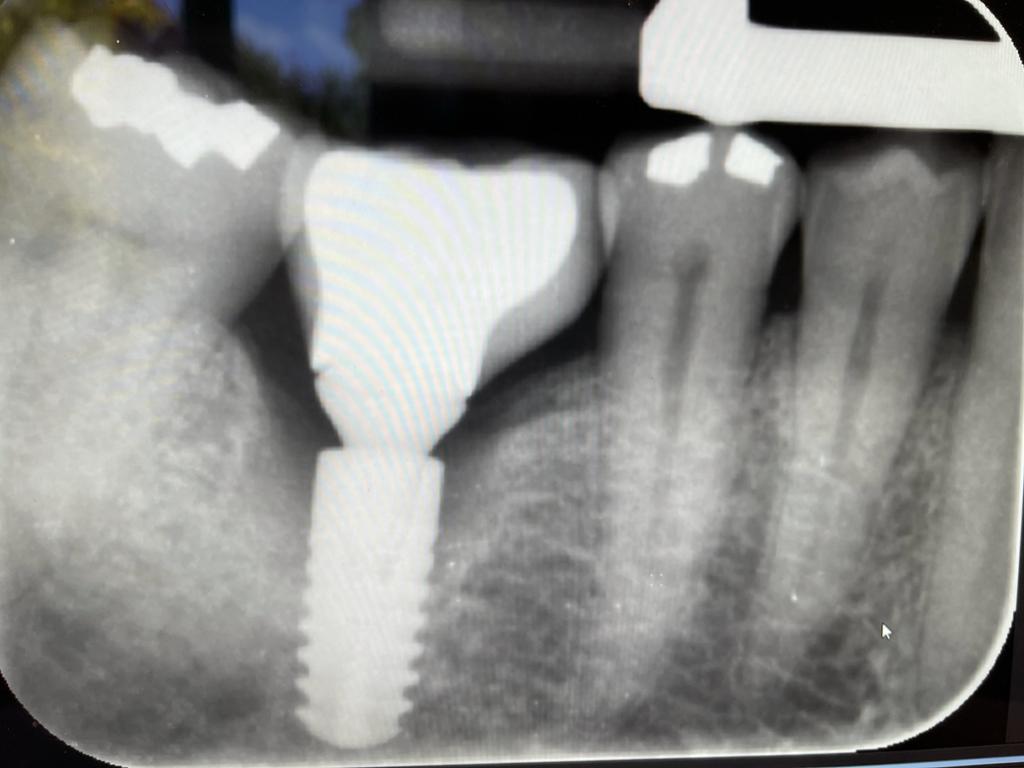

Exceeding all expectations with conservative peri-implantitis management

Dr Senthil describes a treatment plan that helped to save an implant for a patient with bone loss.